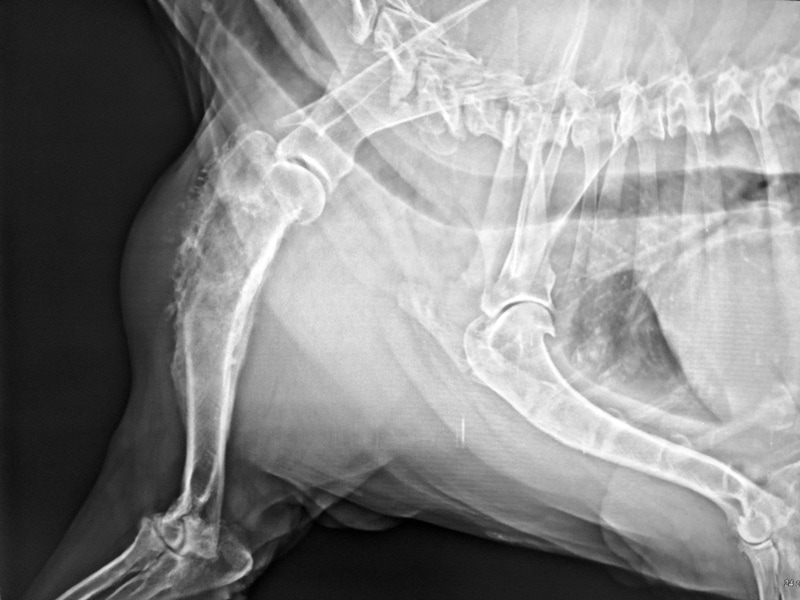

Osteosarcoma

The most common form of bone tumors in dogs, osteosarcoma is almost always fatal. The reason is that by the time a primary lesion is detected, the cancer has spread to the lungs. It is more common in middle-aged, large, or giant breeds, such as the Rottweiler, German Shepherd, Boxer, Doberman Pinscher, and Irish Setter. Although it can affect virtually any bone, the most common locations are the forelimb and hindlimb.

Look for tender areas, pain, or swelling over a bone, which your dog may alert you to by licking the area. Lameness can be mild or severe, or chronic or acute. Because osteosarcoma causes lysis (breakdown) of the bone, it can cause the bone to break (known as a pathological fracture). While any sign of pain or lameness should never be ignored, if you have a large or giant breed dog that is showing signs of pain or lameness, an investigation started early could have a huge impact on your dog’s chances of survival.